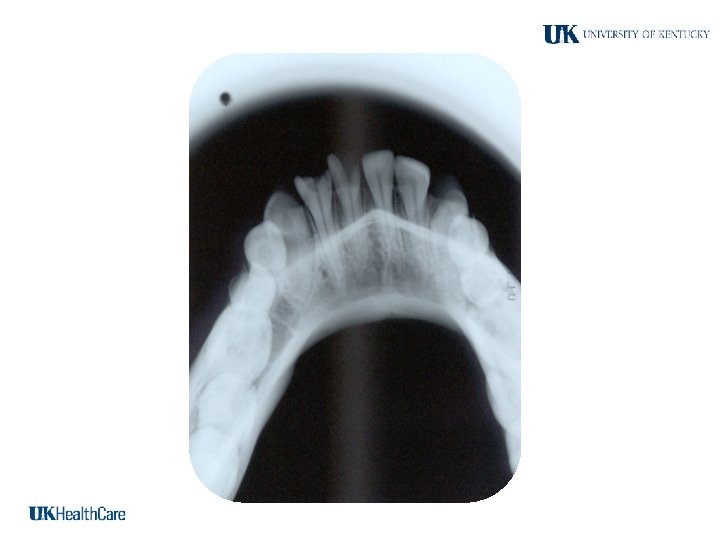

Occlusal Projections

Occlusal Techniques -Occlusal radiographs are named for the fact that the film is placed upon the occlusal surface for exposure -Usually # 4 size films, also called occlusal films -Standardized projections

Maxillary Occlusal Projections Occlusal Mandibular Occlusal Projections

Maxillary Occlusal Views 2. Standard Occlusal View Bridge of the nose Similar to anterior occlusal view Film long axis: Side to side (cross) 70 degrees

Glabellum Standard Occlusal Views 70° Film

Standard occlusal view